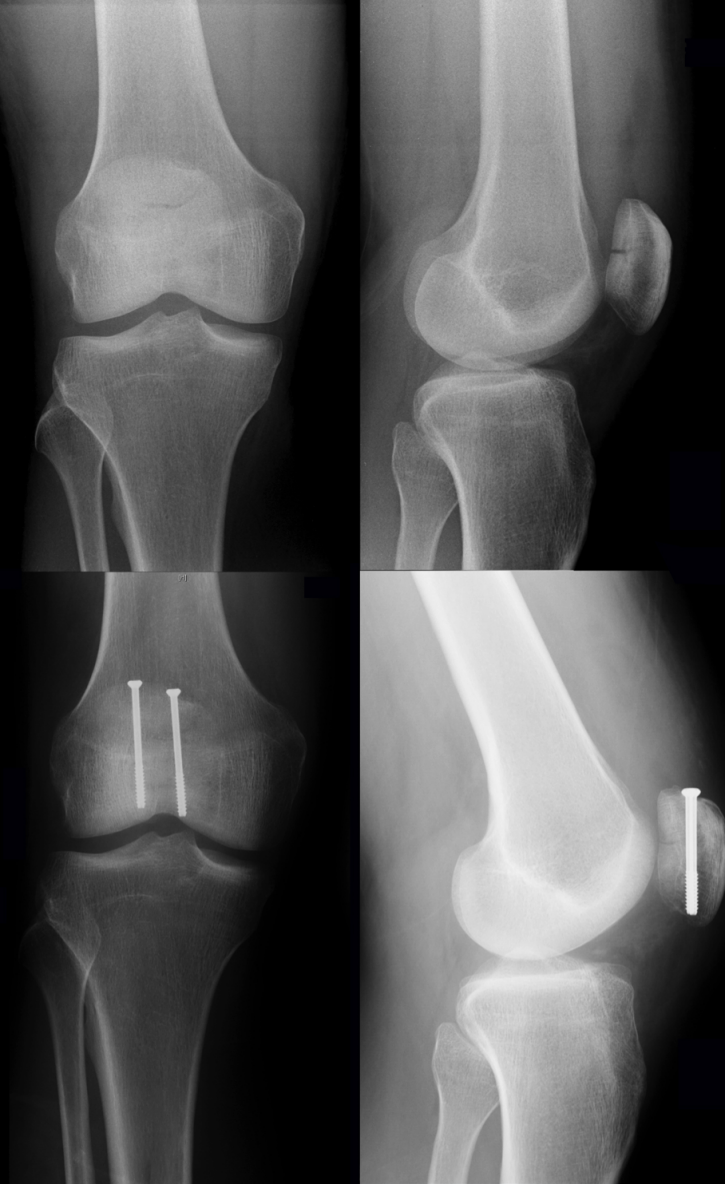

As previously mentioned, every unstable fracture of the patella requires operative intervention. The modified tension band wiring, according to AO principles, is the most accepted and widely used technique for the treatment of displaced fractures of the patella, although several other techniques involving combinations of fixation techniques (i.e. K-wires, screws and cerclage wiring; Figure 3 [Fig. 3]) have been published [8], [60]. From a biomechanical point of view, the surgical procedure aims to neutralize tension forces applied to the patella via the extensor mechanism and convert them into compression forces. For this purpose, at least two K-wires are placed perpendicular to the fracture line and a tension band is applied in an eight-shaped manner to secure reduction. The ends of the K-wires are then twisted and buried in the patella.

Figure 3: Preoperative X-rays of a comminuted patella fracture (above). 3 months post-surgery using a combination out of K-wires, screws, and an eight-shaped cerclage wiring (below).